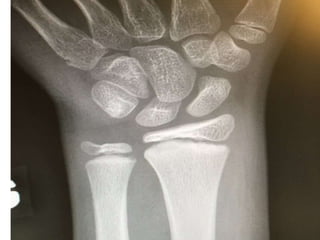

Torus

• Buckle ou motte de beurre

• Fracture la plus fréquente en pédiatrie

Pediatric wrist buckle fractures. Should we just splint and go?

Plint AC et Al. CMEJ 2004.

• 309 Fractures en Torus

• 0 déplacé

• 11 % Complications du plâtre

A randomized, controlled trial of removable splinting versus

casting for wrist buckle fractures in children.

Plint AC1 et Al. Pediatrics 2006

• RCT 87 patients

• Plâtre vs Atelle

• Guérison idem

• Meilleur satisfaction groupe Atelle

A RCT of cast versus splint for distal radial buckle fracture

Williams KG et Al.

Ped Emerg Care 2013

• Prospective randomisé avec un

échantillon de convenance

• Plus grande satisfaction avec Atelle

Atelle suffisant